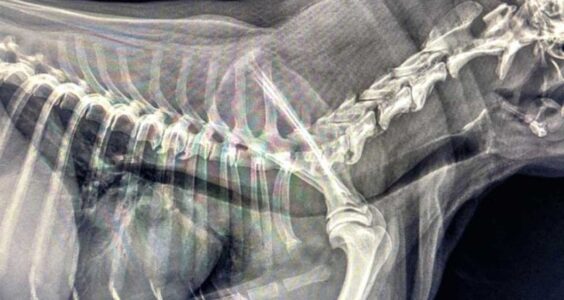

Zapadanie tchawicy u psów (TCS-Tracheal Collapse Syndrome)

Źródło: https://wetgliwice.pl/ Zapadanie tchawicy u psów (TCS-Tracheal Collapse Syndrome) Zapadanie tchawicy u psów (TCS-Tracheal Collapse Syndrome) jest przewlekłą chorobą układu oddechowego …